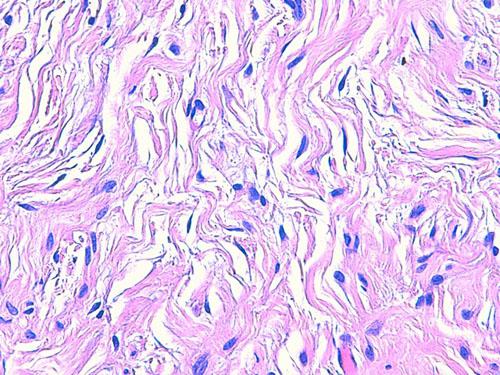

Les nouvelles biopsies mettent en évidence dans le derme profond et l’hypoderme des images identiques de lésions multi-nodulaires, non encapsulées, au sein d’une prolifération cellulaire diffuse de cellules fusiformes. Ces cellules sont peu nombreuses, sans atypie cyto-nucléaire, organisées en faisceaux dans les tissus environnants et les structures annexielles. Ces lésions sont traversées par de nombreuses structures nerveuses périphériques normales. L’épiderme est hyperpigmenté en regard des zones nodulaires (photos 6 à 8).

Photo 8 (HE*1000, LAPVSO) : faisceaux de cellules fusiformes dans un stroma collagénique et myxoïde